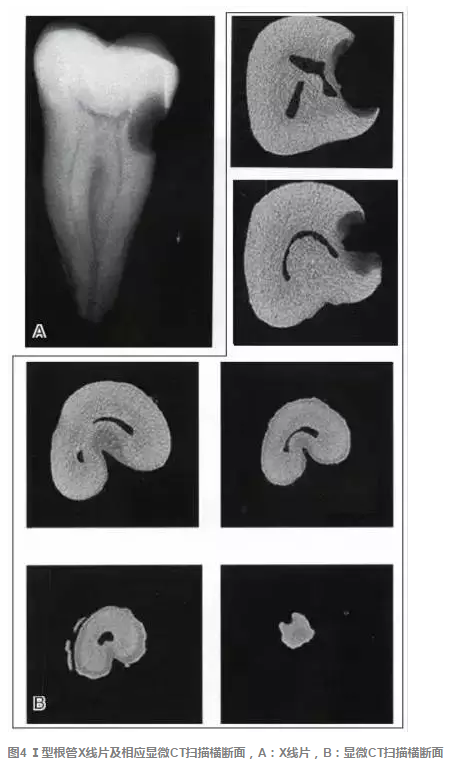

傳統(tǒng)的Melton C形根管分類法雖深化了對根管結構的認識,但由于是基于組織學的分類,不能指導臨床實踐。有學者基于C形根管X 線特征,結合顯微CT掃描結果,提出了一種新的分類方法,便于臨床應用。這種分類方法將下頜第二磨牙分為3型:①Ⅰ型:融合型,X線片上見2個根管,但在根尖區(qū)融合;②Ⅱ型:分離型,X線片上見2個根管且相互獨立;③ Ⅲ型:不對稱型,X線片上雖有2個根管相互獨立,但一長一短,互不對稱(圖3)。各類型C形根管X線特征、顯微CT掃描及重建結果見圖4~9。

圖1 下頜第二磨牙C形根管系統(tǒng)的形態(tài)從根管口到根尖(A~H)可發(fā)生巨大變化